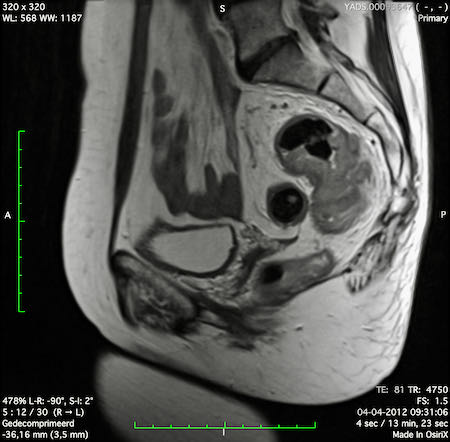

Hình ảnh

Các hình ảnh được cung cấp cho thấy ung thư biểu mô tế bào nhẫn với tình trạng dày lan tỏa thành trực tràng, hình ảnh bia bắn điển hình, và sự xâm lấn mỡ mạc treo trực tràng.